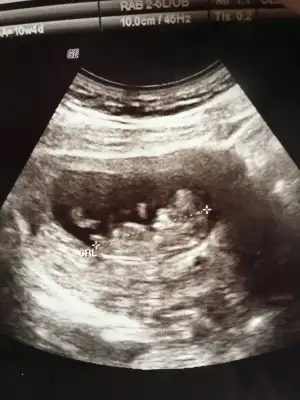

Korkma canım benim korkutmak için söylemedimmm. Bazı bebişler başlarda ilerde bazıları sonradan öyle bir gelişiyor kiYok geç döllenme felan değil. Tam zamanında ilerliyor. Şuanda ne ileri ne geri. 13+2 deyiz. Yani 14. Hafta içerisinde. Doktorum da herşeyin normal ve yolunda olduğunu söyledi. Ense kalınlığımız 1,0 çıktı.

Allah Allah yaa acaba ben mi yanlış anladım ki boy uzunluğunu. Yarın ultrason görüntümden bakıp yazayım tekrar şuanda evde değilim çünkü